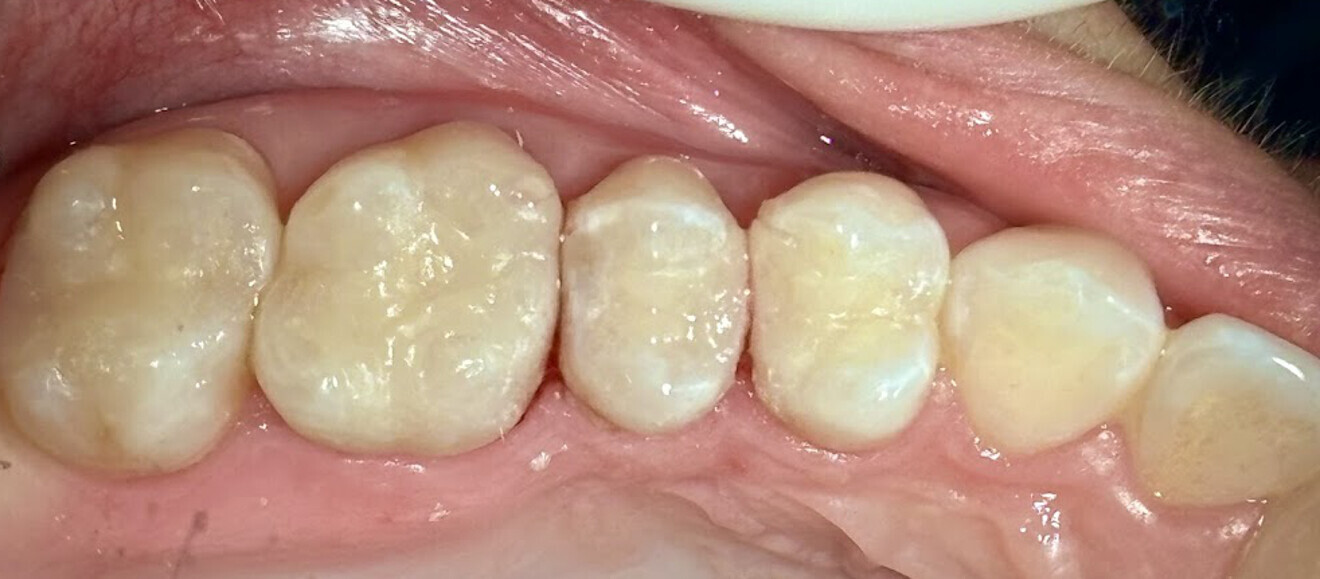

The restorations were taken back to the operatory and tried in to verify fit and seating on the teeth. Once this had been verified, the cementation protocol followed the same procedure detailed in the first case. The completed 3D-printed onlays restored the teeth to natural contours and aesthetics (Fig. 26). A radiograph was taken to confirm marginal adaptation of the luted restorations and elimination of any residual resin cement at the margins (Fig. 27).

Fig. 26: Restorations luted to the prepared teeth after finishing and polishing.